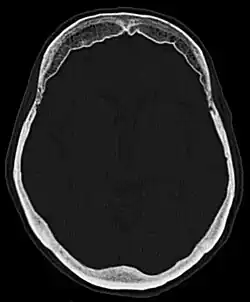

| Hyperostosis frontalis interna in a 74-year-old woman | |

Hyperostosis frontalis interna is a common, benign thickening of the inner side of the frontal bone of the skull. It is found predominantly in women after menopause and is usually asymptomatic. Mostly frequently it is found as an incidental finding discovered during an X-ray or CT scan of the skull.